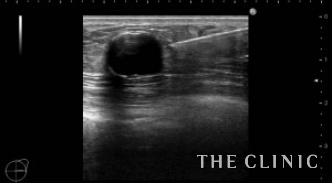

10年前に脂肪注入をされた方です。エコーでみると、右胸の下方に25㎜大のしこりがあり石灰化しています。中身はオイルと古い脂肪です。左胸上方には13㎜大のしこりがあり、中身はオイルです。右の石灰化しているしこりは、被膜が薄いためベイザーで崩していきます。左のしこりは穿刺処置となりました。

右)石灰化しているしこりにベイザーを突き刺します。 左)ベイザーで崩して吸引したあとですが、石灰化しているためカプセルが残存しています。